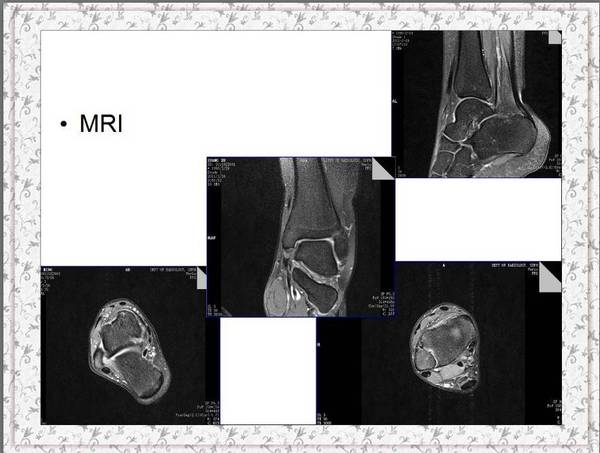

今天康复科李淑媛医生给我们讲了生动的一课。

题目是《慢性踝关节不稳的诊断与治疗》

上传部分课件大家共同分享、学习、进步。